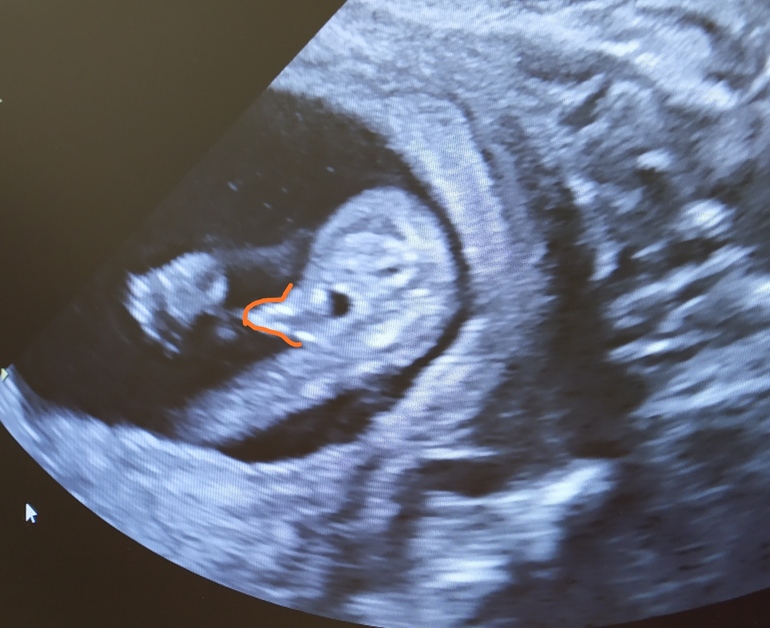

Пол малышаДевочки, вот такое фото есть, с 13-14 недель, предположили мальчика. Как вы думаете, похоже?

То, что вы обвели - половой бугорок, который на этом сроке есть и у мальчиков, и у девочек, там главная разница только в градусе, под которым он расположен, здесь его не видно, на таком сроке надо смотреть сбоку.